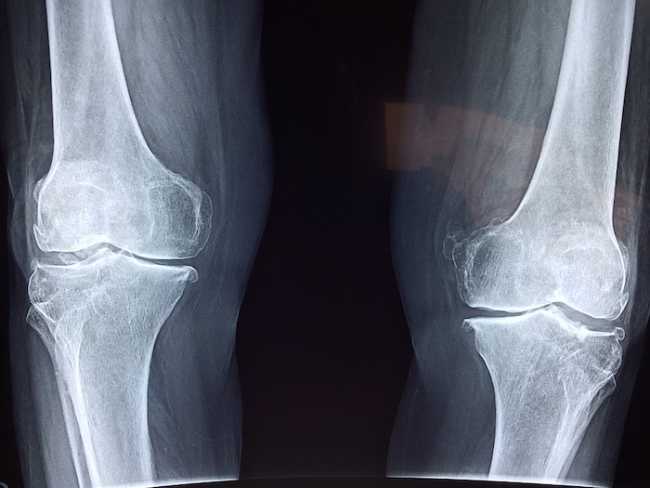

OMEGNA - 21-03-2019 - Si parlerà di protesi al ginocchio nel nuovo appuntamento di Omegna Salute, in programma venerdì 22 marzo, ore 21, al Teatro Oratorio Sacro Cuore. Il dottor Marco Spezia tornerà a illustrare le possibilità offerte ai pazienti dall’ortopedia moderna.

Spezia spiegherà come vengono gestite oggigiorno le patologie del ginocchio in età avanzata. La panoramica, che partirà dalla terapia antinfiammatoria, spazierà dal trattamento infiltrativo per culminare – nei casi più estremi – nell’intervento chirurgico, non sempre e non solo protesico. “Il nuovo appuntamento con il ciclo di incontri patrocinato dal Comune di Omegna con la collaborazione del COQ e di ASL VCO, sarà l’occasione per rivolgersi ai pazienti over 60 interessati a conoscere cosa l’ortopedia moderna può offrire sia in senso conservativo, sia in ottica chirurgica”, spiega il medico.